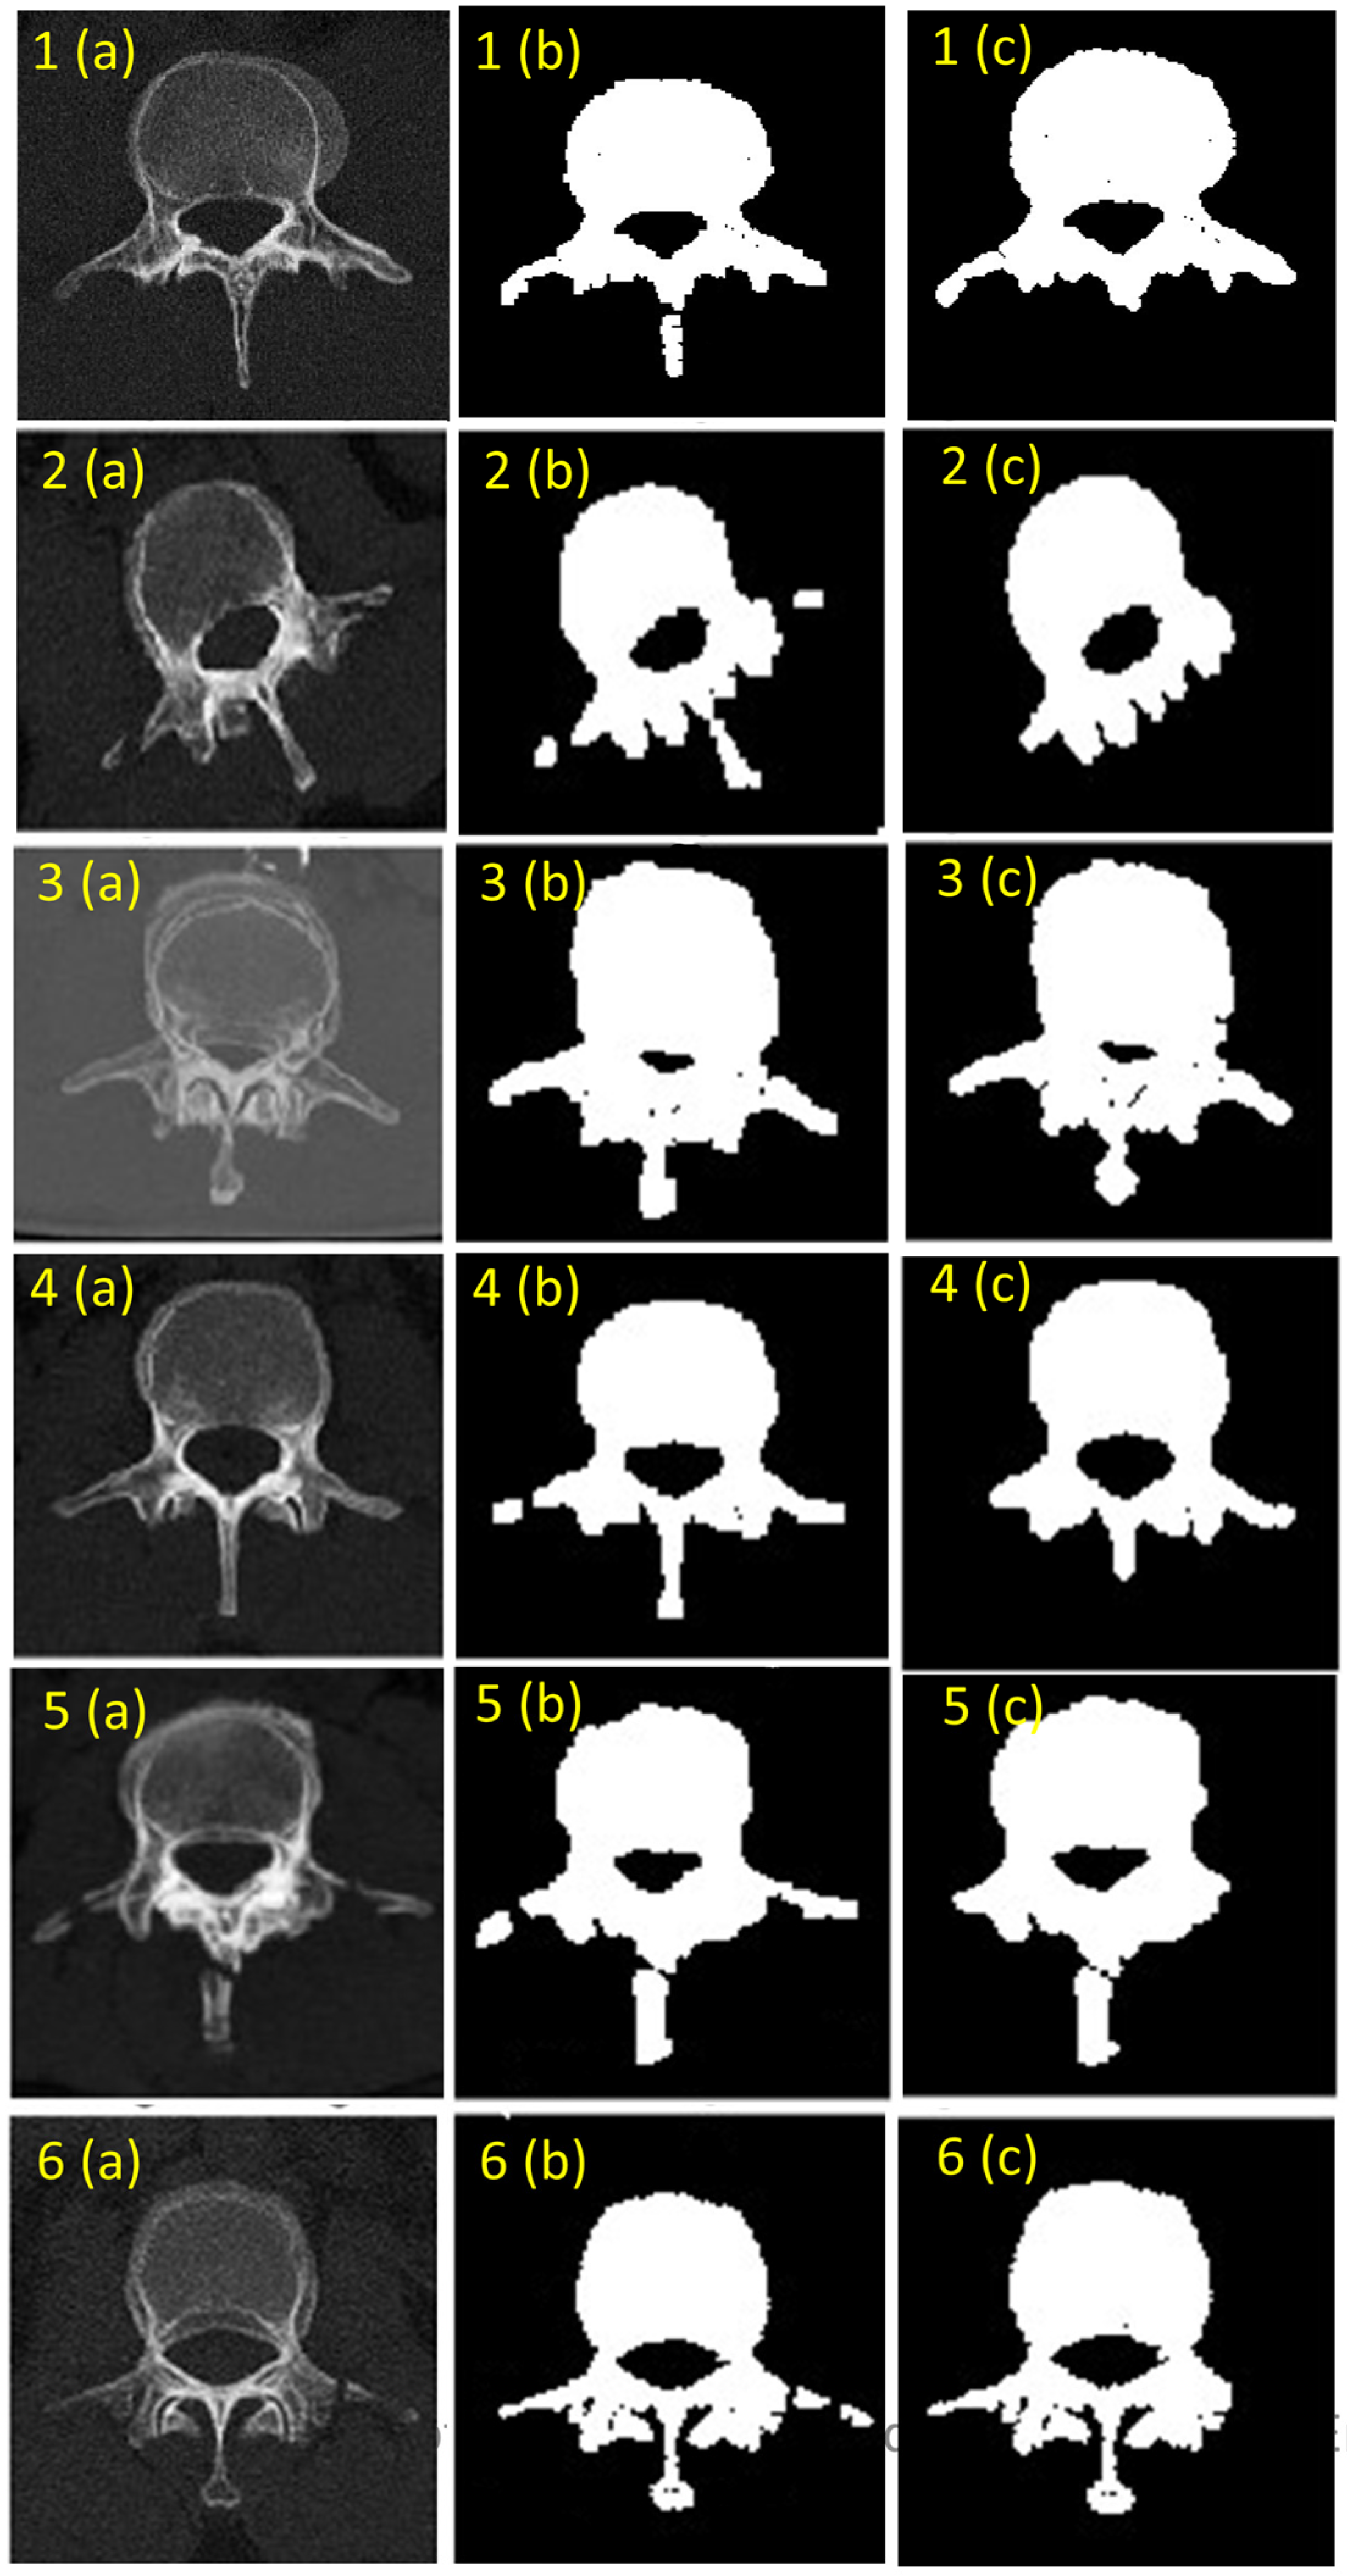

The performance of the Res U-Net model on six patient samples is evaluated using the Dice Similarity Coefficient (DSC), sensitivity, and specificity metrics [28]. In the overall study, a total of 25 patient samples were analyzed to assess the performance of the proposed segmentation framework. However, to maintain clarity and ensure easier readability, we have presented the results from the six best-performing samples in the paper. These six samples were selected as they represent the most accurate and consistent outcomes across various metrics, allowing us to effectively showcase the segmentation capability of the model. The DSC values ranged from 81.42% to 92.23% indicating good overlap between the predicted and actual segmentations with Sample 3 showing the highest DSC at 92.23% demonstrating excellent segmentation performance. Sensitivity values which measure the true positive rate varied from 86.15% to 91.38% indicating that the model effectively identifies the segmented regions correctly with Sample 3 again performing the best. Specificity values representing the true negative rate were consistently high ranging from 90.49% to 98.02% with Sample 3 achieving the highest specificity at 98.02% as shown in Table 1. These results reflect the model’s robustness and reliability in segmenting anatomical structures within CT scans.

Segmentation results for the six patient samples are shown in Figure 6, which includes the original CT scan image, the ground truth, and the segmented output produced by the Res U-Net model. This visualization helps in understanding the qualitative performance of the model alongside quantitative metrics. Ground truth annotations were manually generated to serve as the benchmark for calculating performance metrics [25].

Figure 6. Vertebra segmentation using Res U-Net (a) CT scan image (b) Ground truth (c) Segmented vertebrae.